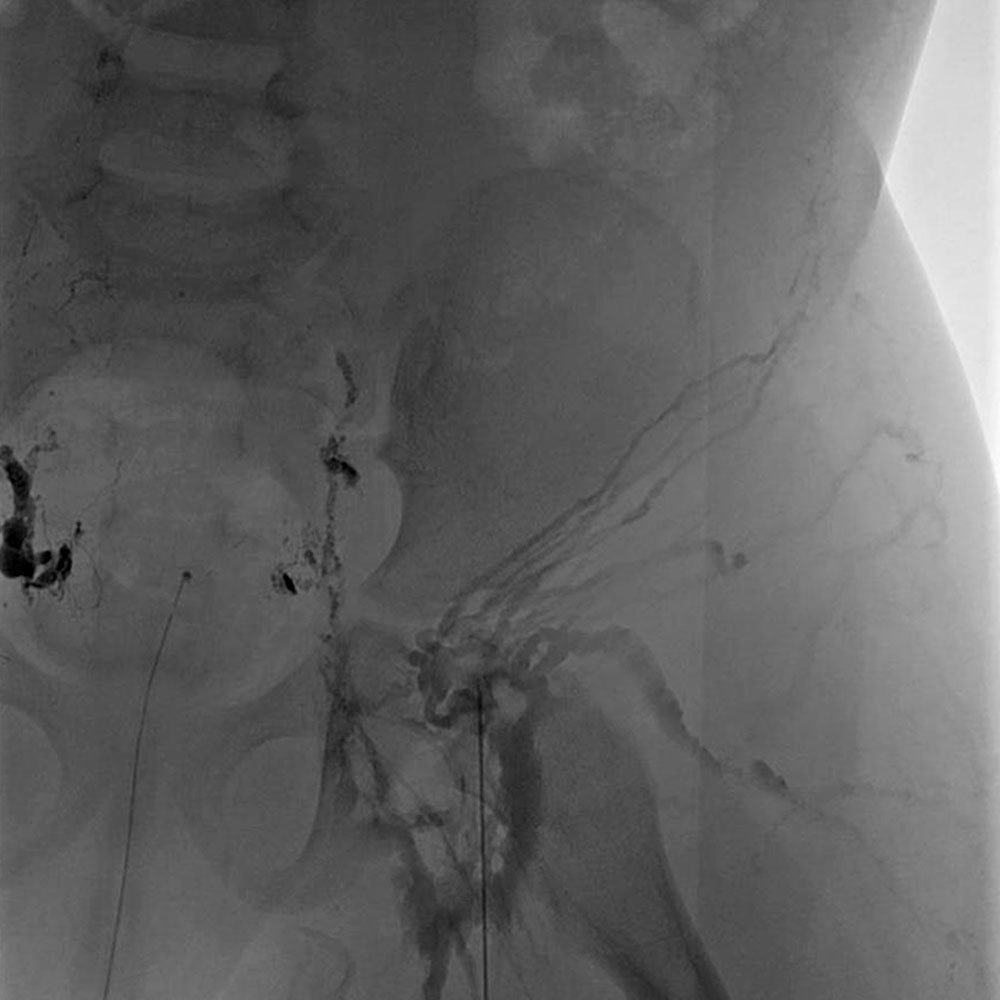

One lymphatic malformation in children that involves the abdomen is Central Conducting Lymphatic Anomaly (CCLA). This is defined as inadequate central drainage of the major trunk lymphatics due to dysmotility, stenosis, or aplasia of the main central abdominal and/or thoracic lymphatic ducts. Insufficient drainage due to congenital malformations of the thoracic duct or cisterna chyli results in lymphostasis with consecutive peripheral lymphatic hypertension and reflux in various organ systems, depending on the location of the drainage obstruction. In this context, thoracic lymphatic hypertension can lead to pulmonary lymphatic hypertension with recurrent chylous pleural effusions or lymphatic congestion of the lungs with plastic bronchitis. Abdominal outflow obstruction (e.g., dysplasia or aplasia of the cisterna chyli) can result in protein-losing enteropathy, chylous ascites, abdominal lymphatic cysts, and/or reflux and retention of lymphatic fluid into one or both extremities (lymphedema of the leg) or the genital region. The pent-up lymphatic pressure can in turn lead to leakage of lymphatic fluid through the skin (lymphorrhea) or cutaneous lymphatic vesicles. Intranodal lymphangiography with ethiodized poppy seed oil injection into a punctured lymph node in the inguinal region can be very helpful in diagnosing this serious condition.